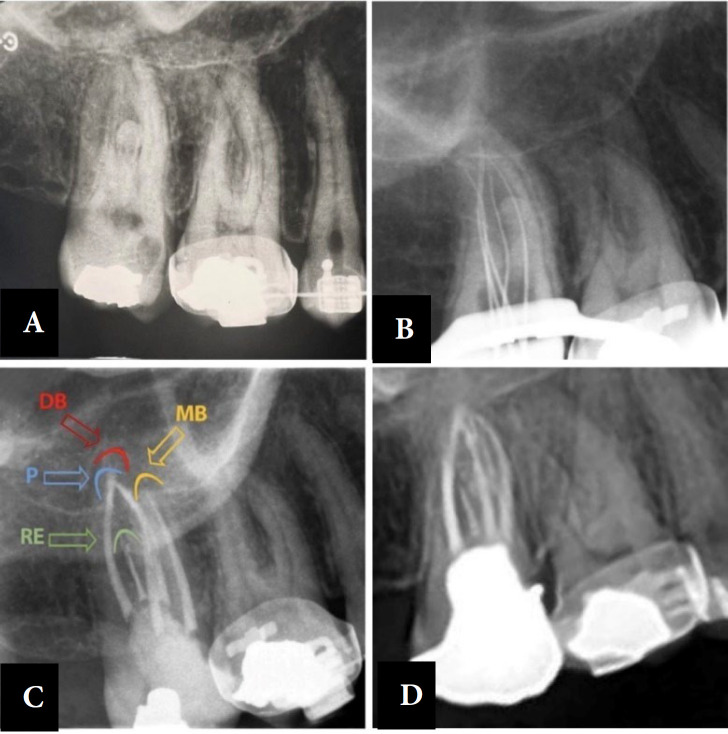

恒上颌第二磨牙的根管治疗由于其根结构的复杂性和根管系统的高度变异,是最成问题的牙齿之一。因此,临床医生应考虑不寻常的根管形态,以减少漏管率。一位三十岁的女性,因右上颌第二磨牙有明显的复发性龋齿,经修复后牙髓坏死而接受根管治疗。术前x线片显示不寻常的形态,并要求进行锥束计算机断层扫描以精确评估根管解剖。本文的主要目的是报道一个五根管上颌第二磨牙,两个腭根管和腭根状牙釉质珍珠管。

Permanent maxillary second molars' root canal treatment due to their root configurations complexity and high root canal systems variations, are one of the most problematic teeth. Accordingly, clinicians should consider unusual canal morphology to reduce the rate of missed canals. A thirty-year-old female was referred for root canal treatment of her maxillary right second molar tooth with obvious recurrent caries under restoration and necrotic pulp. Pre-operative radiographs showed the unusual morphology and cone-beam computed tomography was ordered for precise evaluation of the root canal anatomy. The principal aim of this paper is to report a five-root canals maxillary second molar, with two palatal root canals and a palatal root-like enamel pearl canal.